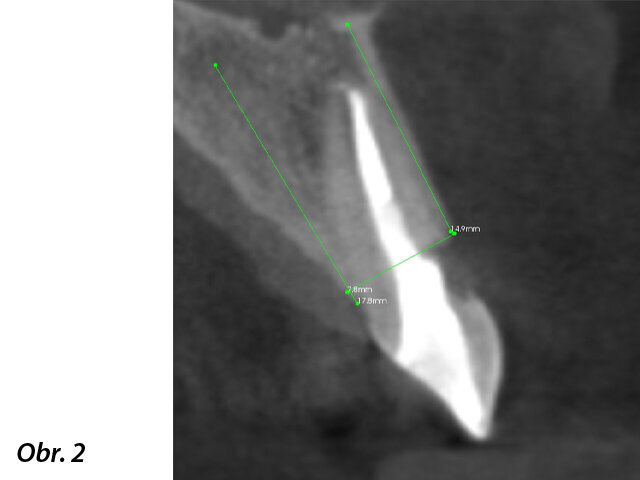

Počáteční stav – zub 11 indikovaný k extrakci.

U pacienta byla naplánována okamžitá implantace s okamžitým zatížením provizorní korunkovou náhradou v estetické zóně. Protokol postupu zahrnoval plánování implantace v programu SIMPLANT, dále vytvoření individuálního abutmentu Atlantis a dočasné e.max keramické korunky ještě před přistoupením k chirurgickému výkonu. Díky tomu bylo v den výkonu možno rychlým a předvídatelným způsobem umístit předem připravenou korunku na právě zavedený implantát s vysoce estetickým výsledkem. Po vhojení implantátu byla s využitím intraorálního skeneru zhotovena definitivní celokeramická náhrada.